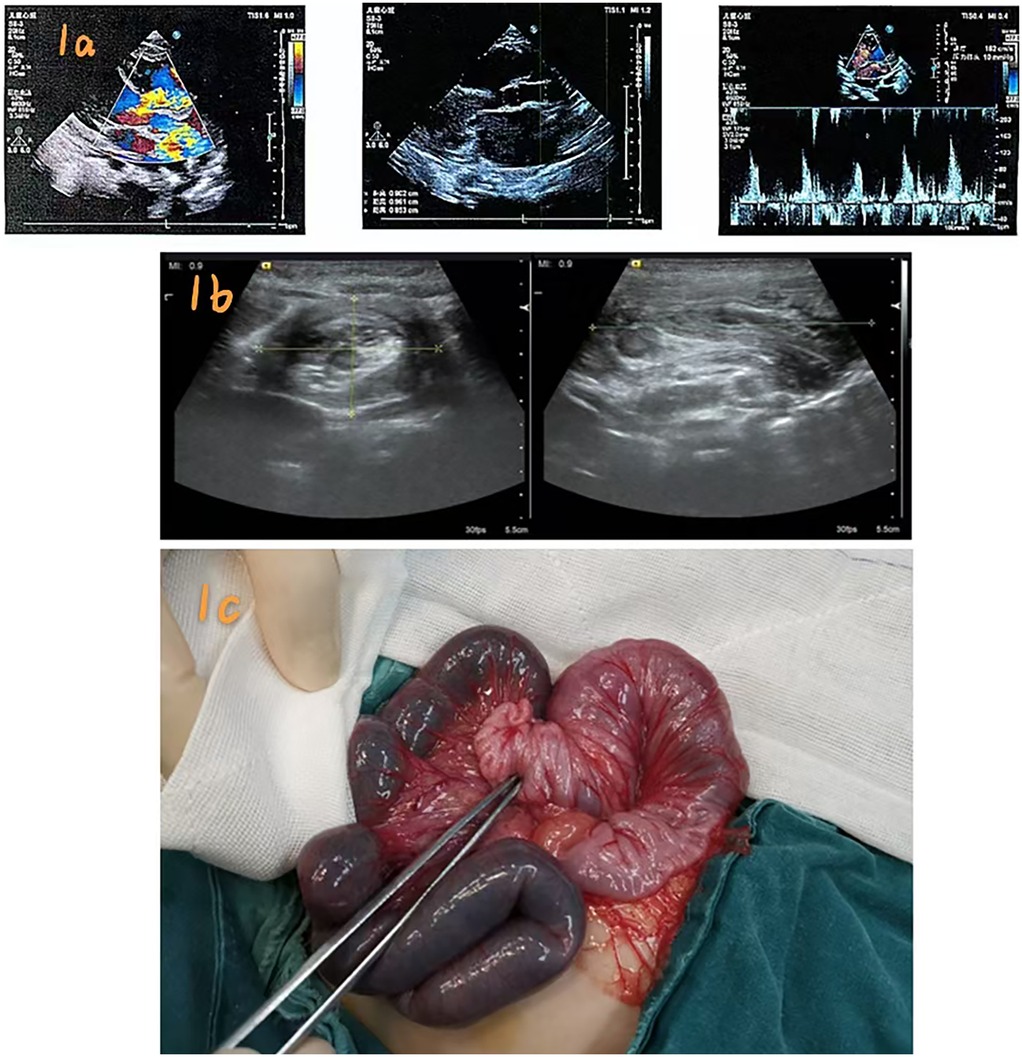

Background: Postoperative intussusception (PI) is a rare but potentially serious complication following congenital heart surgery in infants, often misdiagnosed due to its atypical presentation. Case Presentation: A 3-month-old male infant underwent aortoplasty, ventricular septal defect (VSD) repair, and patent ductus arteriosus (PDA) ligation for congenital heart disease. Approximately 72 hours postoperatively, he developed bloody, jam-like stools. Emergency abdominal ultrasound, the first-line imaging modality, revealed ileocolic intussusception. Three attempts at ultrasound-guided hydrostatic saline enema reduction (pressure: 80 cm H₂O) were unsuccessful, necessitating surgical exploration. Laparotomy identified an 8 cm ileocolic intussusceptum and a 10 cm ischemic ileal segment without a pathological lead point. The necrotic bowel was resected, and an end-to-end anastomosis was performed. The patient recovered uneventfully, was discharged three weeks postoperatively, and demonstrated normal growth at 6-month follow-up. Conclusion: Prompt identification of postoperative intussusception—a rare complication following non-abdominal surgeries like congenital heart disease repair in infants—is of critical importance.